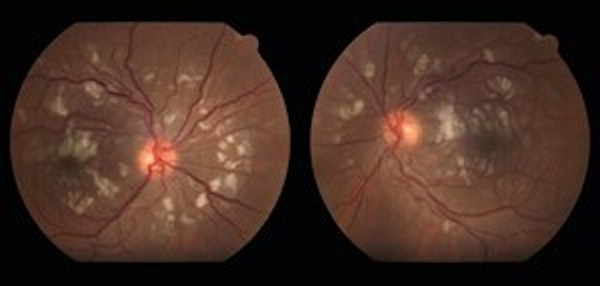

Assessing Characteristics of Patients With or Without Intraocular Inflammation (IOI) In the Brolucizumab Treatment Arms From the HAWK and HARRIER, Phase 3 Studies

• occlusive retinal vasculitis

• Inflammation